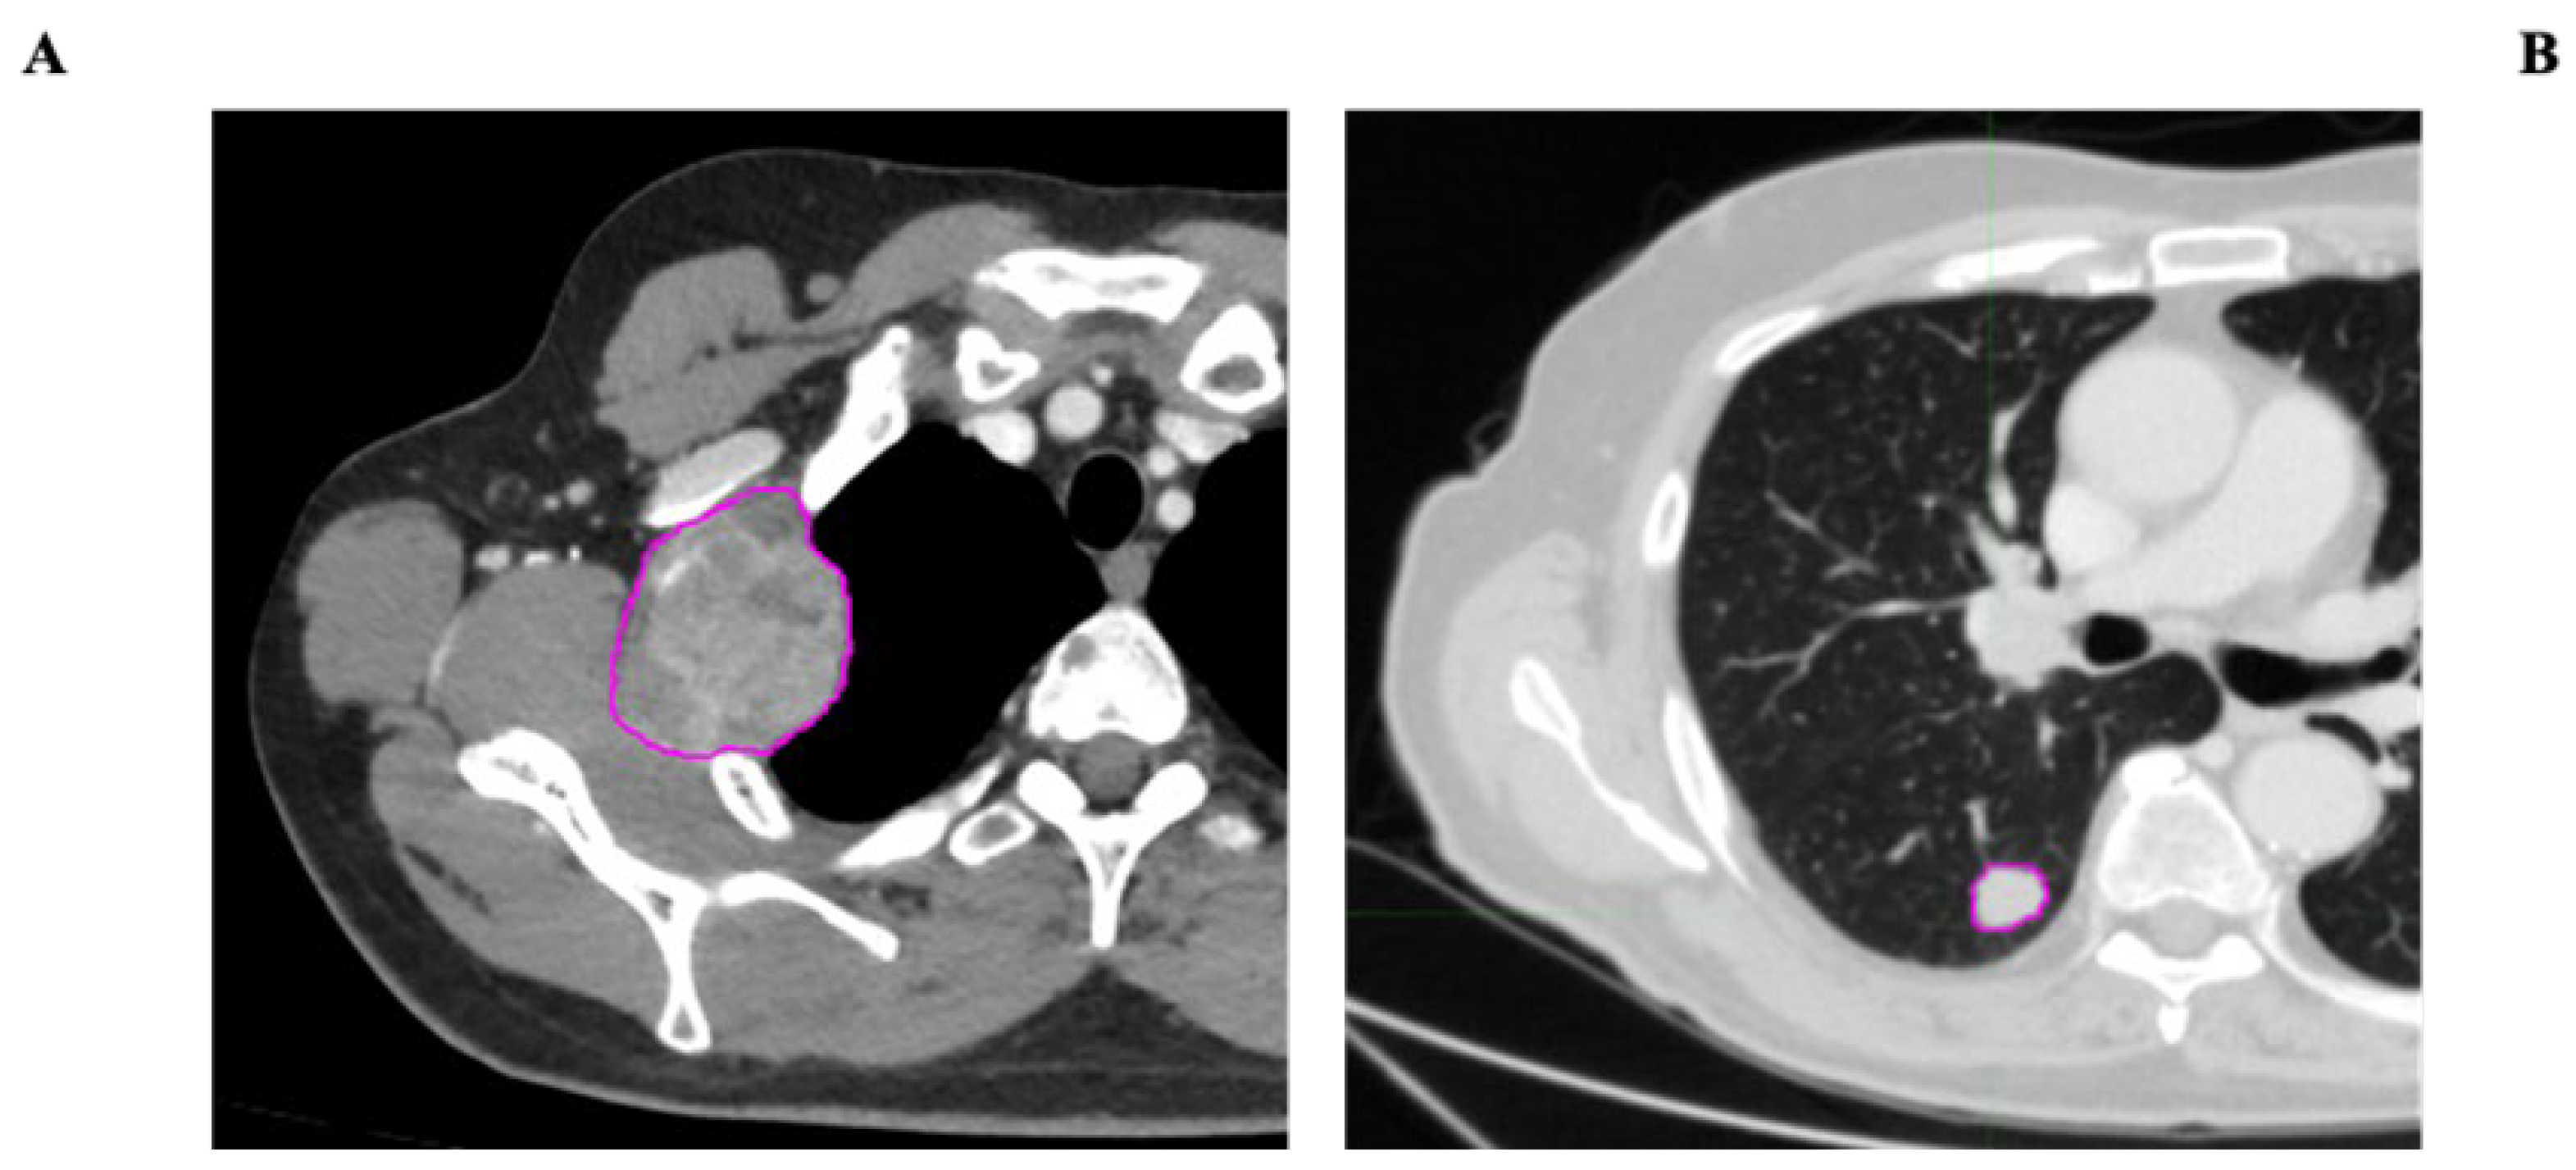

• VOI segmentation: Segmentation of the Volume of Interest (VOI) was performed manually on a slice-by-slice basis in consensus by two expert radiologists in CT imaging (15 and 10 years of experience) using the Trace4Research segmentation tool (named Manual segmentation by an experienced radiologist) (Figure 2).

Figure 2. Examples of metastatic lesion segmentation, with pink contours delineating ROIs (regions of interest). (A) Heterogeneous-density solid lesion of the right lateral thoracic wall. (B) Nodular lesion of the right lung parenchyma.